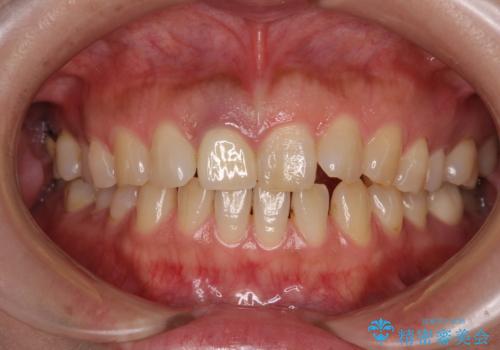

- セラミッククラウンが白すぎる前歯と、放置している奥歯を気にして来院された患者様です。

前歯のセラミッククラウンは将来ホワイトニングをするつもりで白くしたものの、それほど白くならず、ホワイトニングも面倒くさいとのことで白すぎる印象となっていました。

前歯、奥歯ともにオールセラミッククラウンやセラミックインレーにて治療を行うこととしました。

前歯のセラミッククラウンは周りの歯と調和させるためにオーダーメイドタイプのものをおすすめしましたが、元が白すぎていたため、概ね色合いが合えば大丈夫であるとのことで、既製パターンの色調で仕上げました。